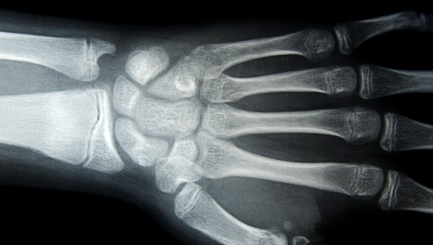

Are You Doing Enough To Prevent Brittle Bones?

Waiting until we get a diagnosis of brittle bones means our bone mineral density (BMD) has already reached a level low enough to cause further problems for our wellness. It is much better for our wellbeing if we start living in a way that can prevent us from getting this condition at all.